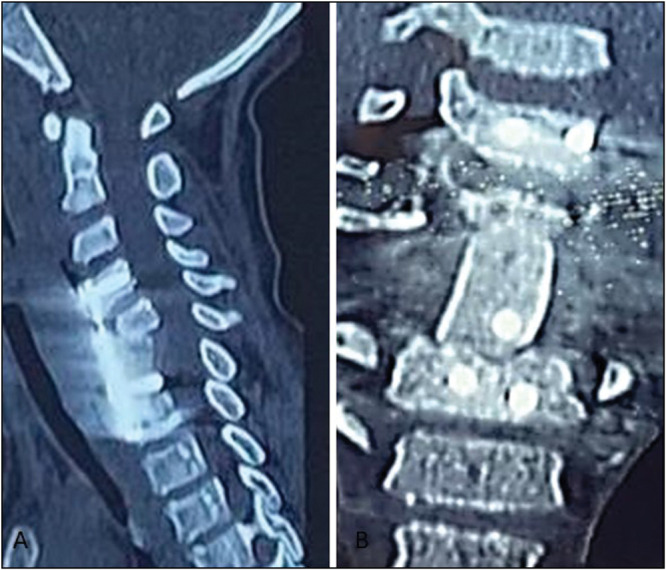

Case report: We describe a case of a 14-year-old male, who was admitted for cervicalgia with incomplete neurological deficit as a result of falling from a tree. Computed tomography (CT) of the neck revealed a posterior C5-C6 spondyloptosis with anterior spondylolisthesis of C7-T1. Surgical intervention was performed by the anterior approach only. The patient recovered completely after 2 months.